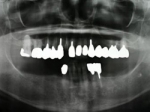

術後レントゲン